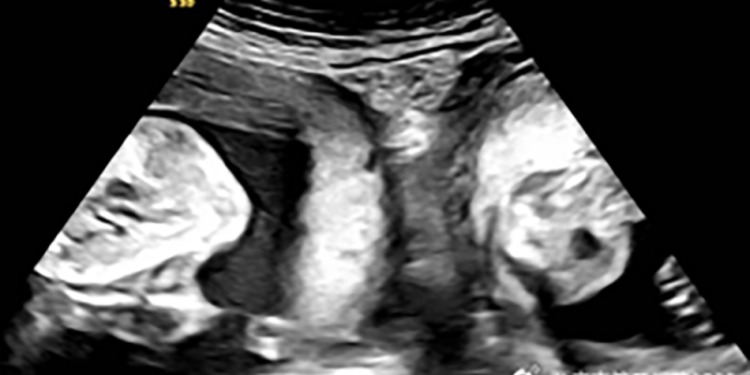

But in January, Li became pregnant again and discovered during an early ultrasound that she was expecting not just one child but twins – one in each womb.